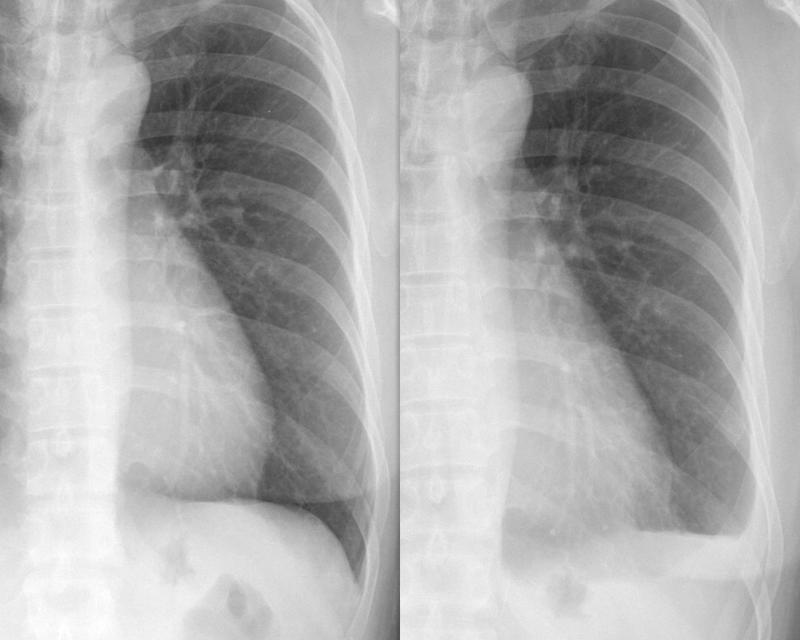

Gallery Pleural small effusion

small effusion